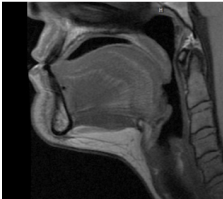

Before

After

Before

After